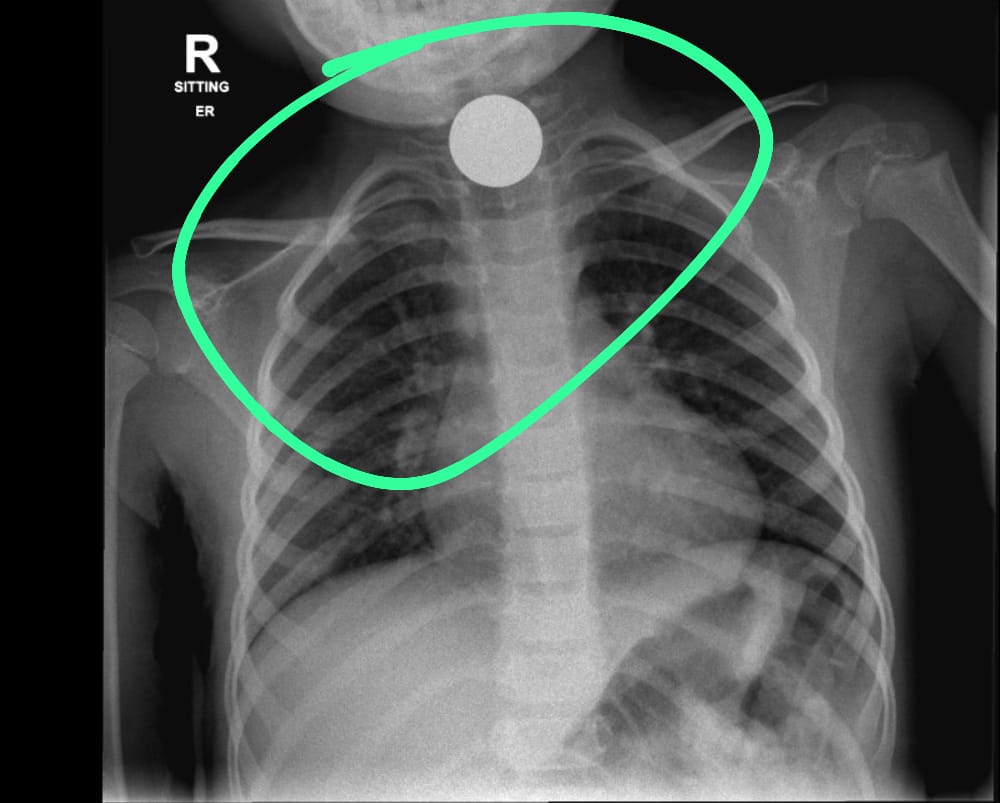

לעומתם, בצילומי רנטגן בילדה בת 7, נמצא כי חלקי המשחק שבלעה התמקמו במעי וגם לאחר 72 שעות טיפול לא הייתה התקדמות בניסיונות לחלץ את חלקי המשחק מגופה ולא נראתה אפשרות ליציאה באופן טבעי. במקרה אחר, הובאה ילדה בת 4 אל בית החולים ובצילום רנטגן נמצאו בוושט של הילדה מטבעות כסף שגרמו לדחיקה של קנה הנשימה , דבר שמנע מהילדה לנשום כראוי.